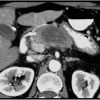

U tụy

» Thông tin: Nữ giới – 57 tuổi.

» Lâm sàng: Sút cân.